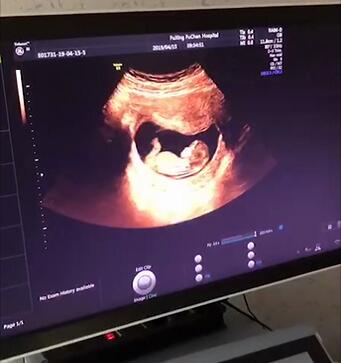

产前检查:NT、唐筛、四维、糖耐都该怎么查?